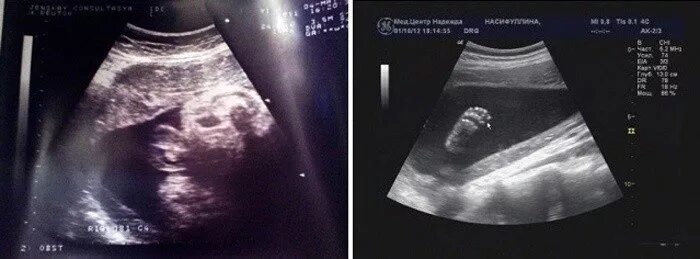

Как выглядит узи живота